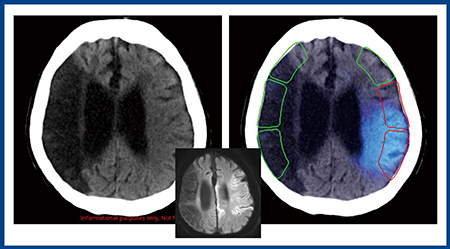

図5では,右のM1,M2と島皮質,およびM3が赤くマッピングされているが,画像を見ると実際にはM2,M3には病巣は及んでいない。実際の臨床では医師が最終確認を行い,虚血サインの判断を修正することができる。また,Ischemia analysisでは,尾状核など深部梗塞も検知できる。

図5 CT-ASPECTSの判定の修正

わずかなズレで加点(M2,M3)されているが,医師が確認し修正することができる。